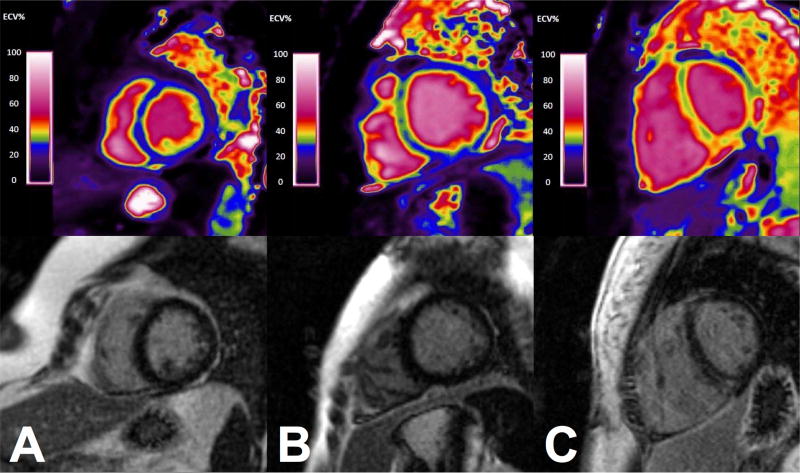

T1 and ECV maps

In selected patients, generation of ECV maps was performed to enable visualization of the spatial distribution of SSc cardiac involvement (Figure 3). T1 maps were generated by applying a novel motion correction algorithm(28), and performing pixel-wise non-linear curve fitting with a three-parameter model. The pre-contrast and post-contrast T1 maps were used to calculate ECV on a per-voxel basis to enable ECV visualization using a custom look-up table. ECV map generation was performed in Matlab (The Mathworks, Natick, MA).

Figure 3.

Extracellular volume maps (top row) and corresponding LGE images (bottom row) in A. control patient, B. an SSc patient without visible LGE, and C. an SSc patient with visible LGE.

ECV mapping enabled visual assessment of myocardial fibrosis that was sometimes disparate from LGE imaging (Fig. 3).